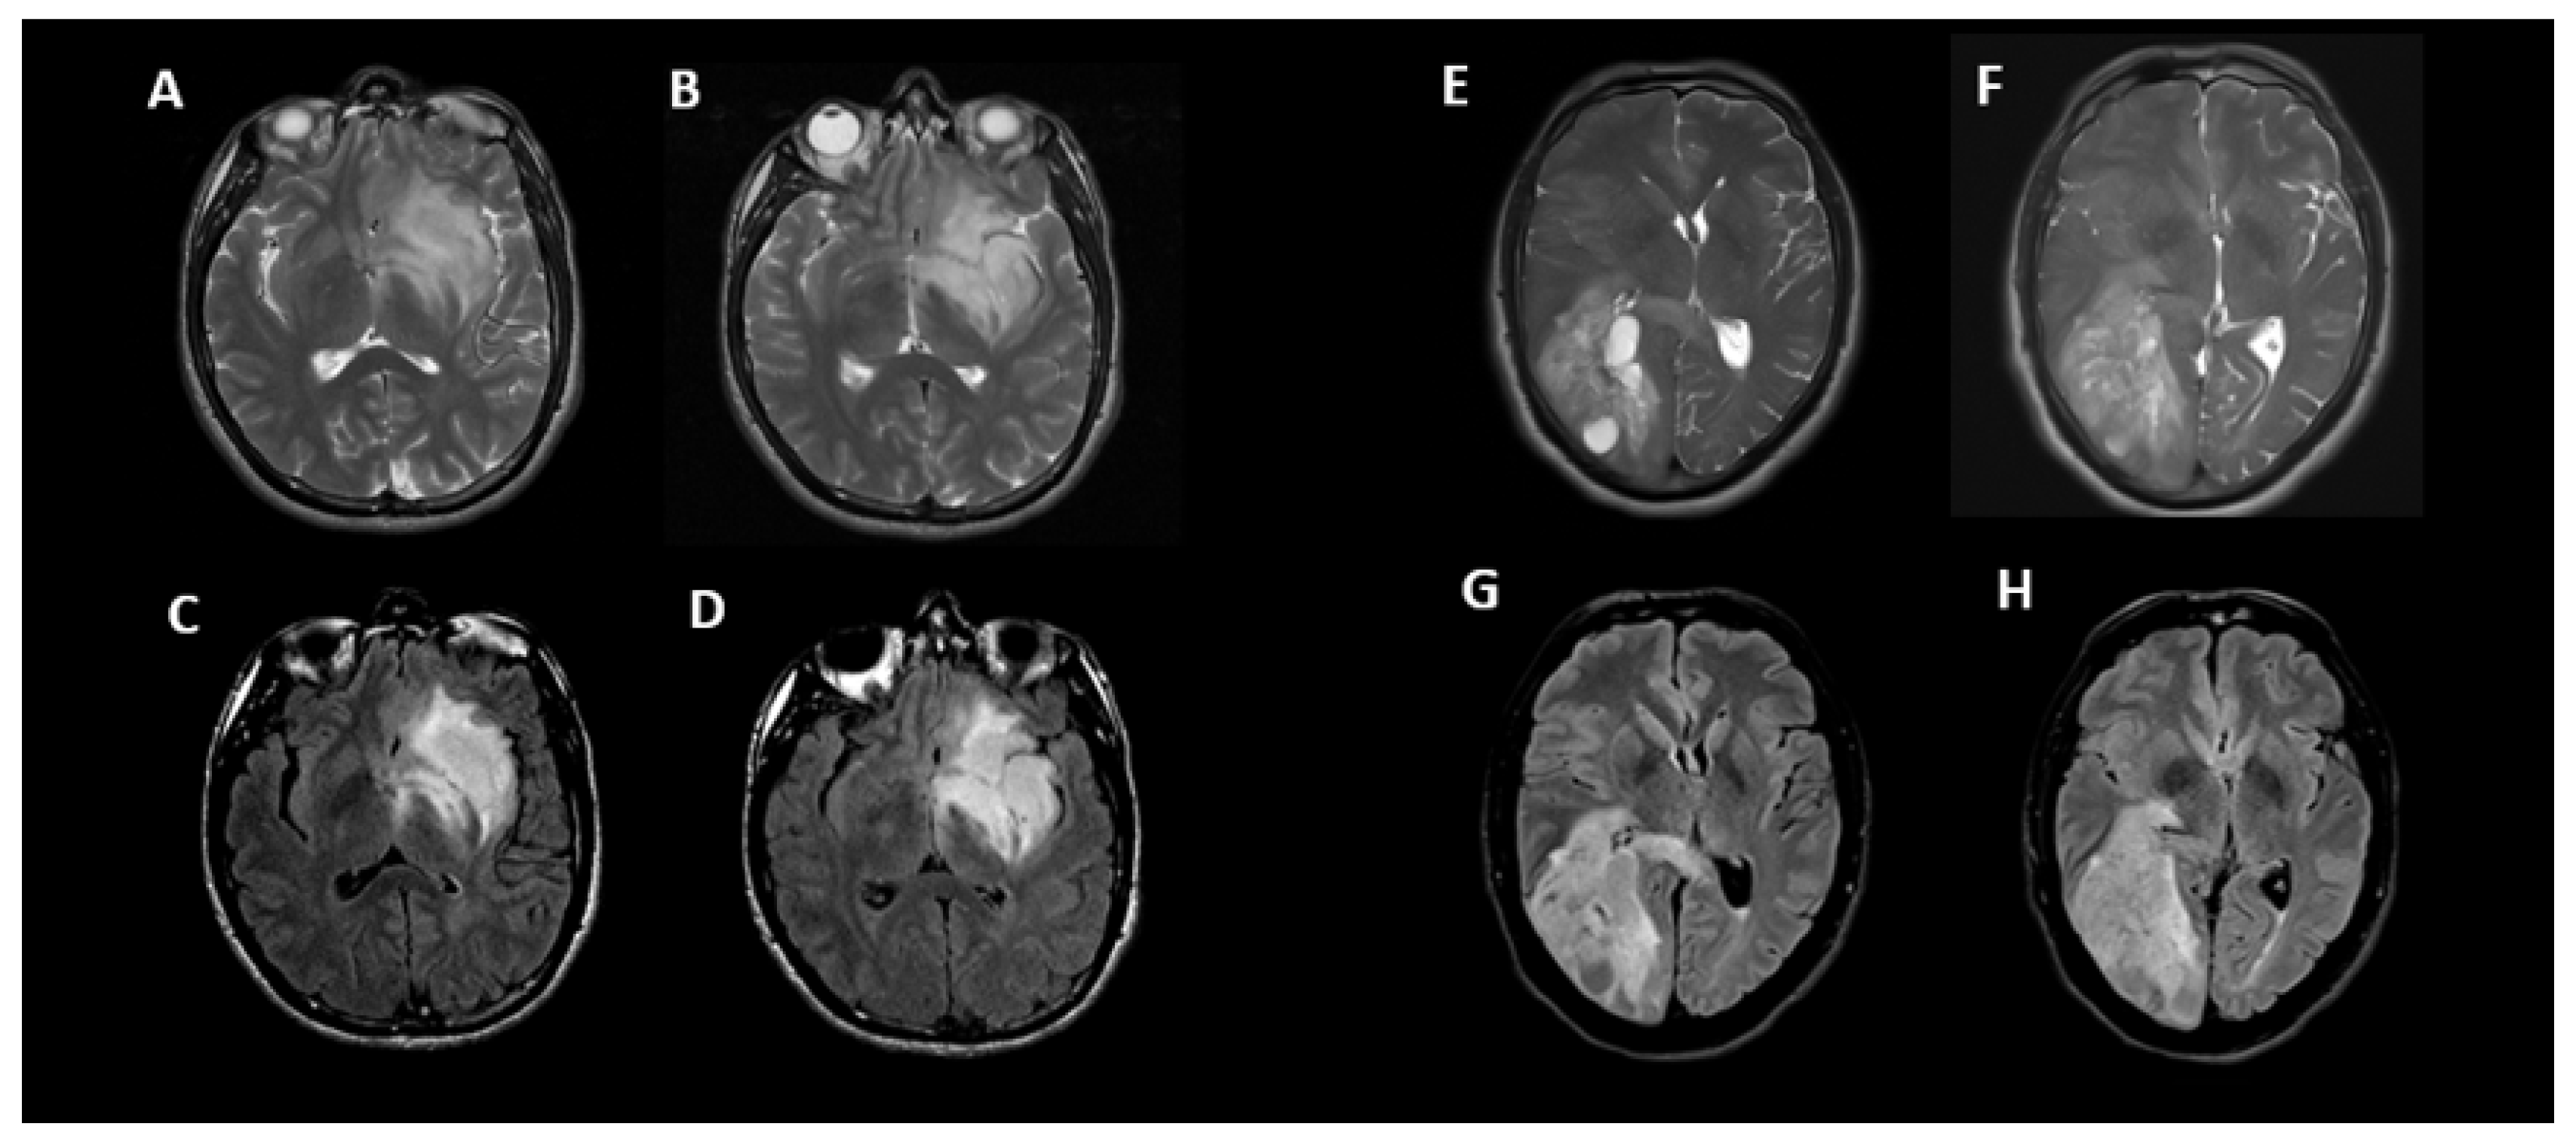

2.3. Image Analysis

3.2. T2-FLAIR-Mismatch-Based Prediction of 1p/19q Co-Deletion Status

3.3. Radiomic-Based Prediction of 1p/19q Co-Deletion Status